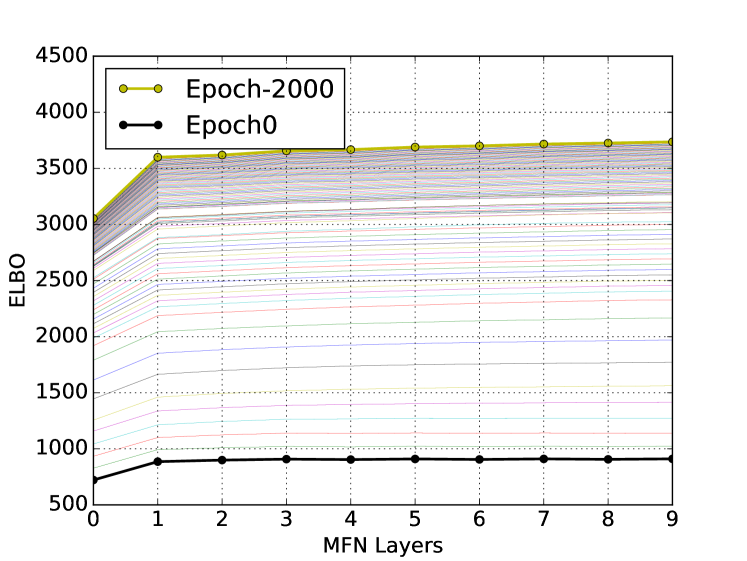

We create sub-images comprising of nodes (batch) from each image and derive the corresponding adjacency matrices to reduce memory footprint during the training procedure. Parameters of the MFN are learned by minimizing the BCE loss in (8) computed using all batches of all images in the training data using back-propagation with Adam optimiser with recommended settings [8]. To further reduce computational overhead we restrict the neighbourhood of each node to be nearest neighbours based on Euclidean distance of their locations in the image data. Based on initial investigations of ELBO we set the number of layers in MFN, . The learning curves for loss and binary accuracy are shown in Figure 1, along with the ELBO plot showing the successive increase in ELBO with each iteration within an epoch (as guaranteed by MFA) and with increasing epochs (due to gradient descent).